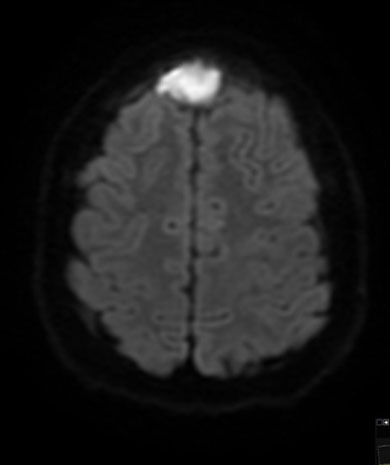

Symptoms typically have an indolent onset, starting with low fevers and headache, and progressing to vomiting and neurologic changes. A head CT or magnetic resonance imaging (MRI) of the brain allows for an accurate diagnosis. See Figures 9 A-B for a brain MRI that depicts the typical findings of abscesses secondary to Streptococcus. Figures 10 A-C show a classic epidural abscess. Given the possibility of elevated intracranial pressure, lumbar puncture should be avoided because of the risk of herniation.

Figure 10C. Epidural Abscess |

![]() |

Diffusion-weighted magnetic resonance imaging of midline epidural abscess Used with permission from Mark Warren, DO, Dayton Children’s Hospital. |